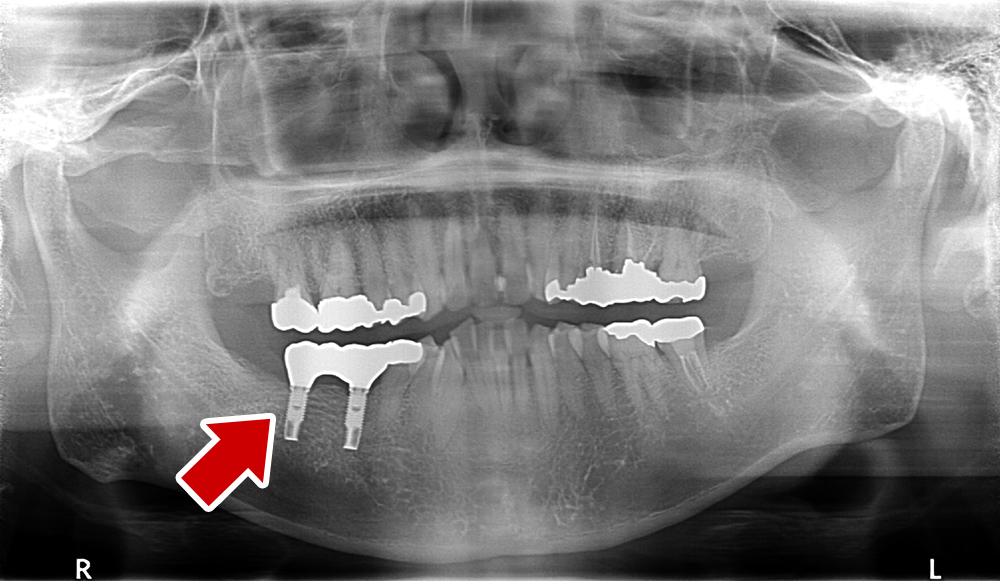

58歳 男性 歯科医療関係者紹介

- 主訴

- 右下を抜歯して噛めない

- 処置内容

- インプラント2本埋入

- 治療費用

- 約80万円(税込)

- 治療期間

-

8か月

仮歯完成まで5か月(この時点で噛めます)、+3か月で最終素材へ

- リスク

- 上部構造物、仮歯の破折、術後の腫れ(3日)、人工歯根脱落リスクがあります